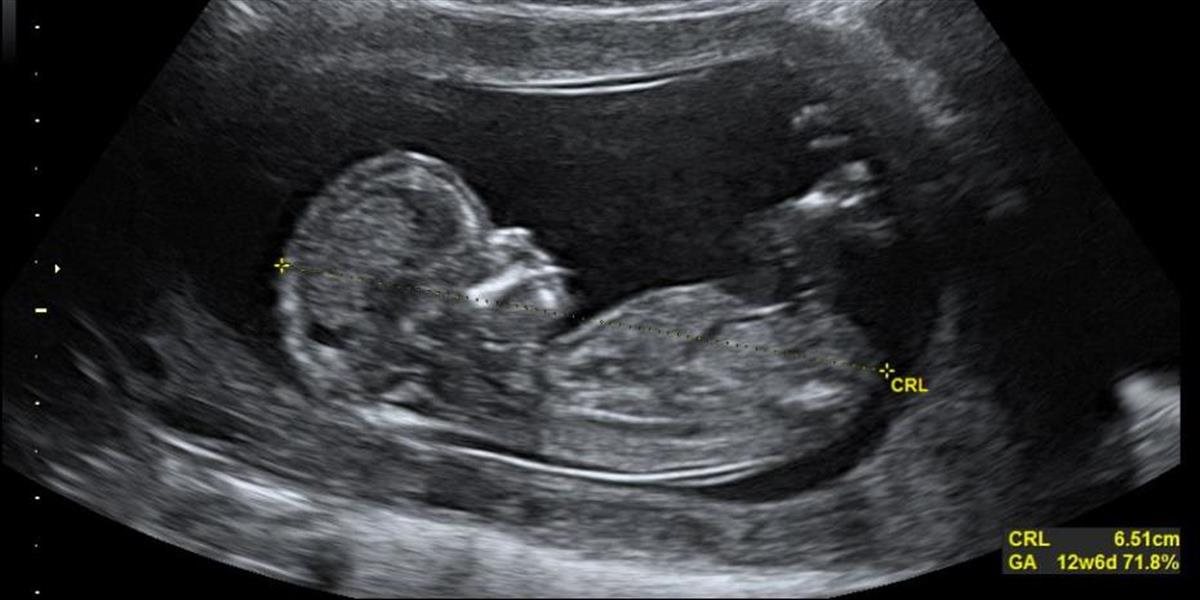

Tehotná išla na ultrazvuk a zistila, že dieťatko je chlapček. „Bola som v šoku, plakala som a myslela som si, že je to prekliatie.“ napísala o svojom tehotenstve. Ako napísala, nechcela priviezť ďalšie „monštrum“ do tohto sveta, a tak sa rozhodla ísť na potrat.